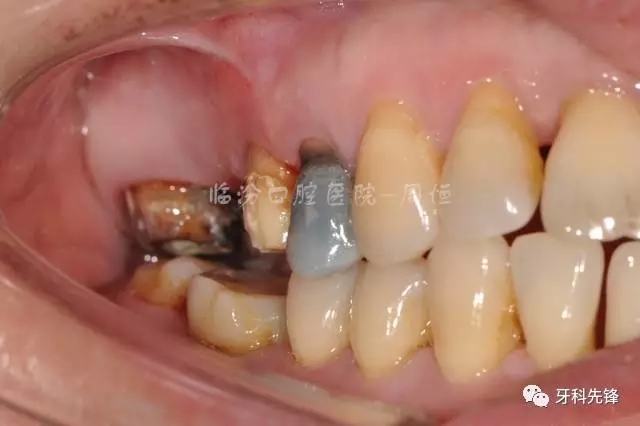

圖5拆除原修復(fù)體側(cè)位咬合照

640.webp (6).jpg